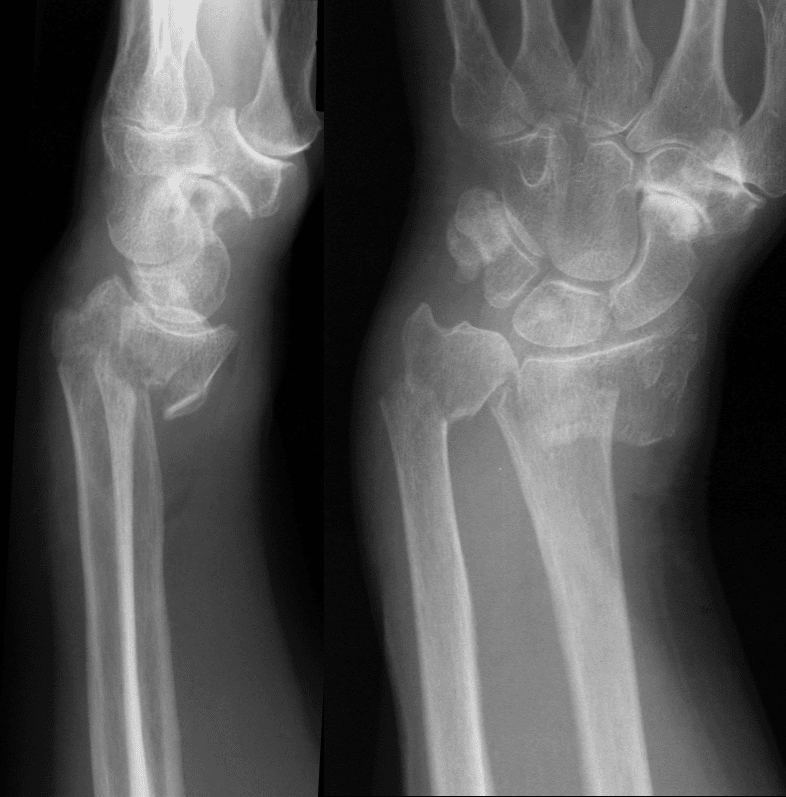

डॉक्टर सबसे पहले आपकी कोहनी और बाजू की जांच करेंगे। उसके बाद आपसे इसके कारण और लक्षणों के बारे में जाना जाएगा। इसके बाद आपके फ्रैक्चर की स्थिति जानने के लिए X-Ray की सलाह दी जाती है। X-Ray से इस बात का पता चल सकता है कि क्या आपकी हड्डी टूटी है या अन्य कोई कारण है जिससे आपको दर्द और अन्य समस्याएं हो रही हैं। यही नहीं, इससे डॉक्टर आपकी समस्या के बेहतरीन उपचार के बारे में भी जान पाएंगे।

स्मिथ फ्रैक्चर को रिवर्स कॉल फ्रैक्चर या गोयरंड स्मिथ फ्रैक्चर भी कहा जाता है। इस फ्रैक्चर में डिस्टल फोरआर्म शामिल है। रेडियस बाजू की दो हड्डियों में सबसे बड़ा है। इस फ्रैक्चर का नाम डबलिन, आयरलैंड के एक सर्जन रोबर्ट विलियम स्मिथ के नाम पर पड़ा है। स्मिथ फ्रैक्चर भी, पाल्मर एंज्यूलेशन के साथ संबंधित है। इसका मतलब है कि इसमें हड्डी का टूटा हुआ टुकड़ा हथेली की दिशा में विस्थापित होता है।